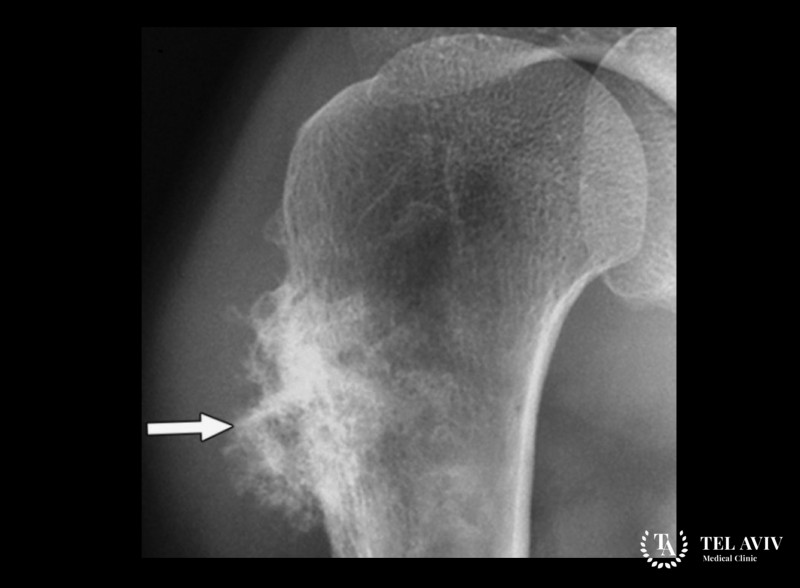

- Рентгенография.